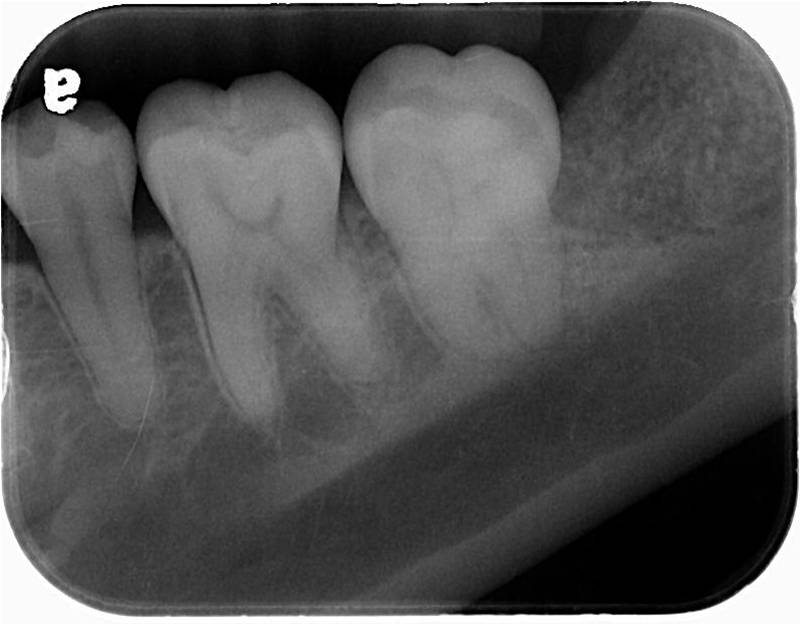

治療前,環口X光檢查,#38牙齒位不正

X光可見骨修復